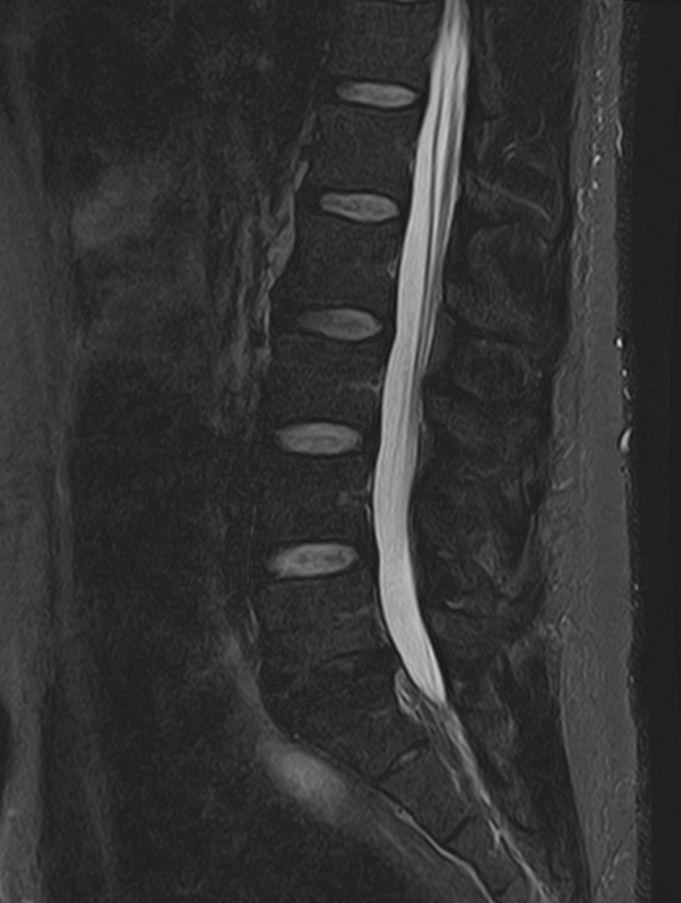

Наиболее точным и эффективным способом диагностики причин появления болей в нижней части спины является МРТ. С помощью данного метода можно оценить состояние всех анатомических структур позвоночного столба на исследуемом уровне, диагностировать поражение позвоночника на начальной стадии, когда другие методы не дают результатов. Такой патологией, в частности, является сакроилеит (воспаление крестцово-подвздошного сочленения), который часто становится причиной анкилоза (сращения) или нестабильности (патологической подвижности) сустава. Выявление сакроилеита на ранней стадии значительно улучшает прогноз в плане лечения и профилактики осложнений.

В клинике «Доступная медицина» диагностика патологии нижней части спины осуществляется на высокотехнологичном оборудовании – новейшем высокопольном томографе TOSHIBA VANTAGE TITAN 1,5 Тесла, который обеспечивает высочайшее качество изображений, точность и достоверность полученных данных. Магнитно-резонансная томография осуществляется без применения ионизирующего излучения, поэтому является безопасным методом обследования и может применяться неоднократно по мере необходимости.

Что можно диагностировать при проведении МРТ пояснично-крестцового отдела позвоночника + МРТ крестцово-подвздошных сочленений

При проведении данного комплексного обследования можно выявить:

• дегенеративно-дистрофические заболевания позвоночника: спондилез, спондилоартроз, остеохондроз;

• стеноз (сужение) позвоночного канала;

• грыжи межпозвонковых дисков (протрузии, экструзии);

• переломы позвонков, их смещение;

• спондилиты, гнойные артриты, сакроилеит, абсцессы околопозвоночных тканей и другие воспалительные заболевания, туберкулез;

• опухоли позвоночника и окружающих тканей;

• патологические изгибы позвоночника, сколиоз, усиленный или выпрямленный лордоз как нарушение статической функции позвоночника;

• аномалии строении позвоночника.